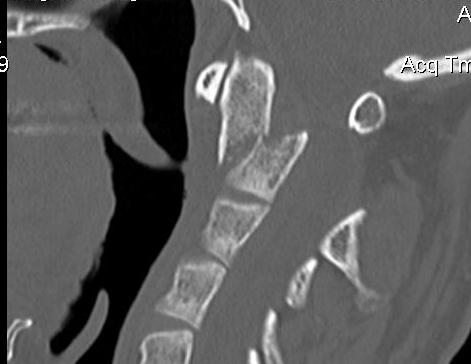

Anatomy

Superior projecting bony element of C2 / axis

C1 / atlas rotates around the dens to provide cervical rotation

Type 2

Fracture of base of odontoid process

- most common type

- > 50%

Type II Dens Fracture

Type III

Definition

Through the body of C2

May involve portions of C1 or C2 facets

High healing potential